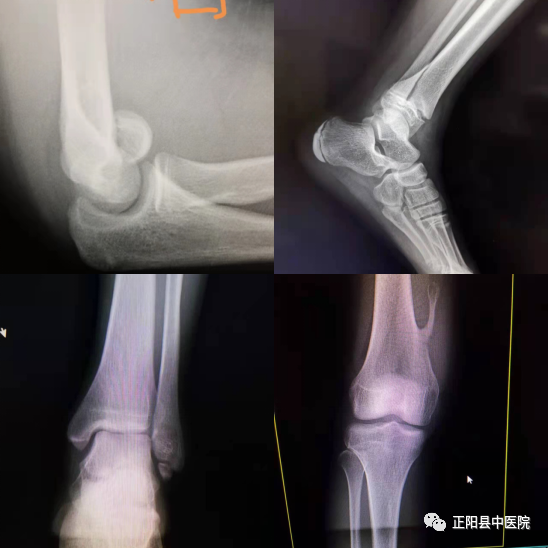

下面我们可以看几个实战中的病例图片(插图〉。在以上的病例中,单凭一张正位片或者是侧位片,你能做出正确的诊断吗?很显然不能达到诊断的目的,会出现漏诊现象。所以在实际工作中,放射科的四肢关节X线摄影技术是有原则性要求的,从众多四肢关节原则中列举几条吧:第一,病人体位要舒适,拍片时需要静止不动,防止产生运动伪影;第二,常规拍片为正位和侧位,最好放于同一张照片上,便于比较。第三,儿童的四肢关节拍片一般需要两侧同时摄影,便于鉴别诊断。如双侧腕关节、双侧膝关节、双侧髋关节等等。